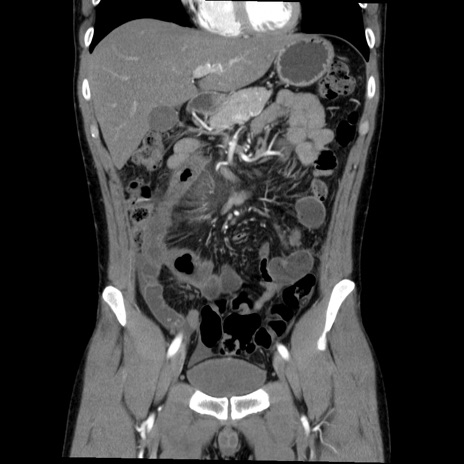

症例36(冠状断像)

【症例】20歳代 男性

【主訴】心窩部痛

【現病歴】今朝より上腹部痛あり。一旦軽快していたが再度出現したため救急要請。昨日夕に白身の魚を含む刺身を食べた。

【身体所見】BP 136/89mmHg、HR 74/min、BT 37.0℃、腹部:膨満、軟、心窩部に圧痛あり。反跳痛なし、筋性防御なし、腸雑音やや亢進あり。

【データ】WBC 17700、CRP 0.48